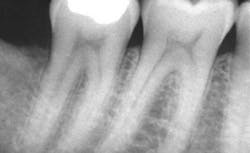

For example, a person might visit a dental hygienist after a year without preventive care. Documentation from the prior office may indicate healthy gingiva and no evident caries. By performing an assessment, the dental hygienist now identifies plaque in areas floss fails to reach because calculus blocks the client’s otherwise thorough home care techniques. In the areas retaining plaque, the dental hygienist diagnoses gingivitis, and in one area, decalcified tooth structure at risk of progressing to a cavity on a tooth already compromised by a large restoration. A reasonable treatment plan for that new client is a prophylaxis and fluoride treatment every six months, and bitewing radiographs once a year. The average cost for those services is $385 per year in the Los Angeles area.11